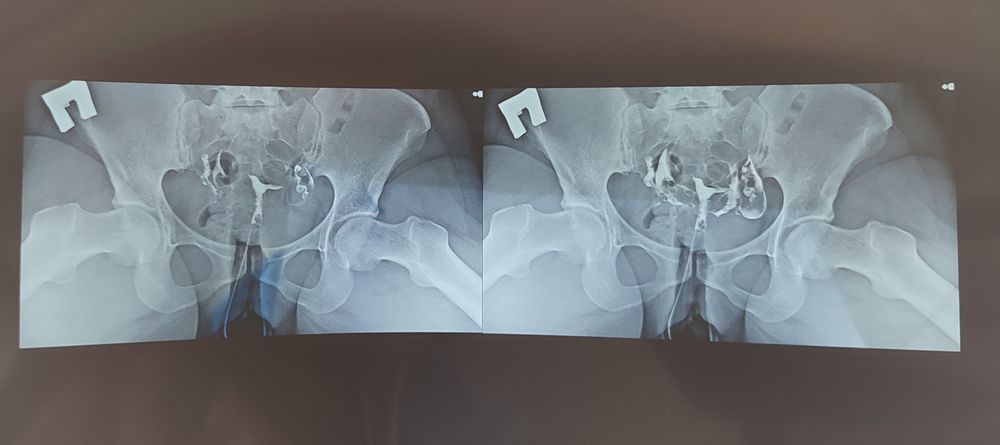

ГСГ делали под рентгеном в Чудо доктор.

Во время исследования было лишь неприятно, когда вставляли канюлю, чуть укололо в этот момент, и когда только начали подавать контраст, начало чуть распирать, но потом все прошло. При повторном вводе контраста я уже ничего не ощущала. Трубы проходимы обе. Врач сказала, что в случае непроходимости, я бы перенесла намного хуже.

Я, правда, правую трубу на снимке почти не могу найти, но видно, что жидкость вышла.